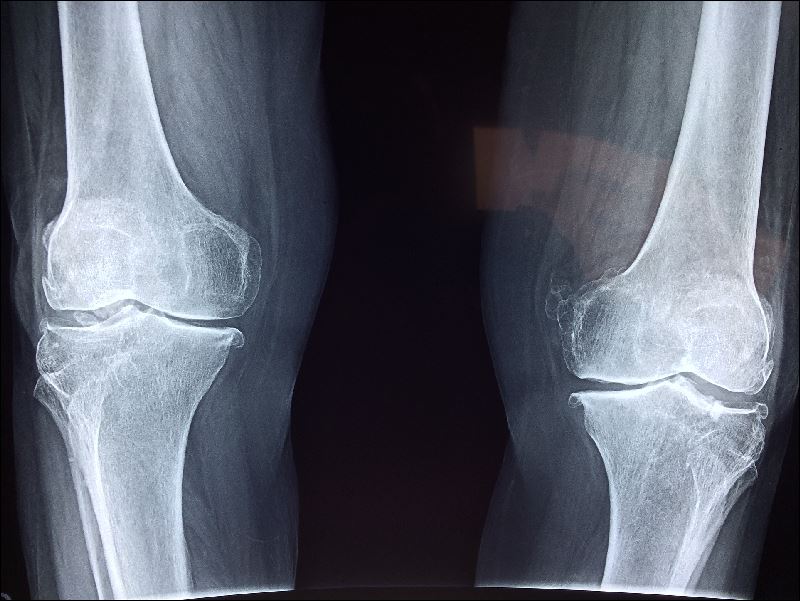

골다공증 유병률의 성별·연대별 뼈의 신진 대사 뼈는 한번 만들어지면 그 후 변하지 않는 것으로 여겨지지만,

사실 오래되고 열화된 뼈는 유지 보수되어 새로운 뼈로 다시 태어나고 있습니다.이 것이 뼈의 신진대사입니다.

또는 뼈의 리모델링이라고도 합니다. 건강한 뼈에서는 뼈 흡수(뼈를 망가뜨리는 기능)와 뼈 형성(뼈를 만드는 기능)의 밸런스가 균형을 이루고 있습니다. 그러나 골다공증 뼈는 뼈 흡수가 점점 진행되어 뼈 형성을 웃돌아 버려 뼈가 스산해지고 약해집니다.

골다공증 유병률의 성별·연대별 폐경기 후 여성호르몬 저하 골다공증은 특히 여성에게 많은 질병으로 환자의 80% 이상이 여성으로 알려져 있습니다.

여성 호르몬의 일종인 에스트로겐은 뼈의 신진 대사 시에 뼈 흡수를 완화하여 뼈에서 칼슘이 녹아 나오는 것을 억제하는 작용이 있습니다. 따라서 폐경기를 맞아 여성호르몬의 분비가 감소하면 급격히 골밀도가 줄어들어

같은 연령대의 남성에 비해 골밀도가 빠르게 낮아집니다. 여성 골밀도의 변화 무리한 다이어트나 운동부족 등의 생활습관 다이어트로 인한 영양 부족은 골다공증의 원인이 됩니다. 특히 성장기는 튼튼한 뼈를 만들고 뼈에 칼슘을 저축하는 중요한 시기이므로 극단적인 다이어트를 하면 미래의 골밀도에 악영향을 미칩니다.